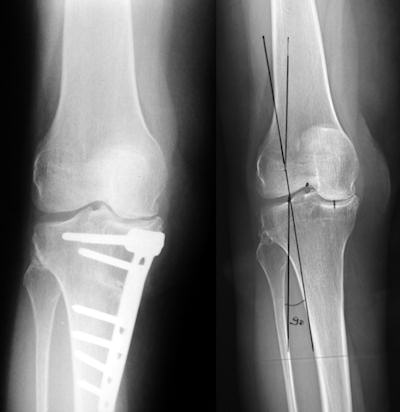

Hastalığın erken dönemlerinde kullanılır. Kapalı ameliyat yöntemi ve küçük kesilerden bir kamera yardımı ile eklem içine girilip, yıkama, saçaklanmış kıkırdakların temizlenmesi, serbest cisimlerin çıkartılması ve menisküs yırtıklarının düzeltilmesi gibi işlemler yapılır. Hastaların şikayetlerinde 6 ay ila 5 yıl arasında süren bir rahatlama sağlar. Hastalığın doğal seyrini değiştirmez, ileri derecede hasarlı eklemlerde faydasızdır.Kemik Düzeltici Ameliyatlar

Hastalık orta derecede ilerlemişse yük taşıyan eklemlerde yapılır. Amaç, eklemin aşınmış bölgesine binen aşırı yükü ortadan kaldırıp, yükü sağlam tarafa aktarmaktır. Bunun için kemik kesilerek düzeltilir ve uygun açıya getirilerek tespit edilir. Tespit için genellikle metal-plak vidalar kullanılır. Protez yapılmasının uygun olmadığı genç hastalarda zaman kazanmak için tercih edilir, 5-7 yıllık bir rahatlama sağlar.